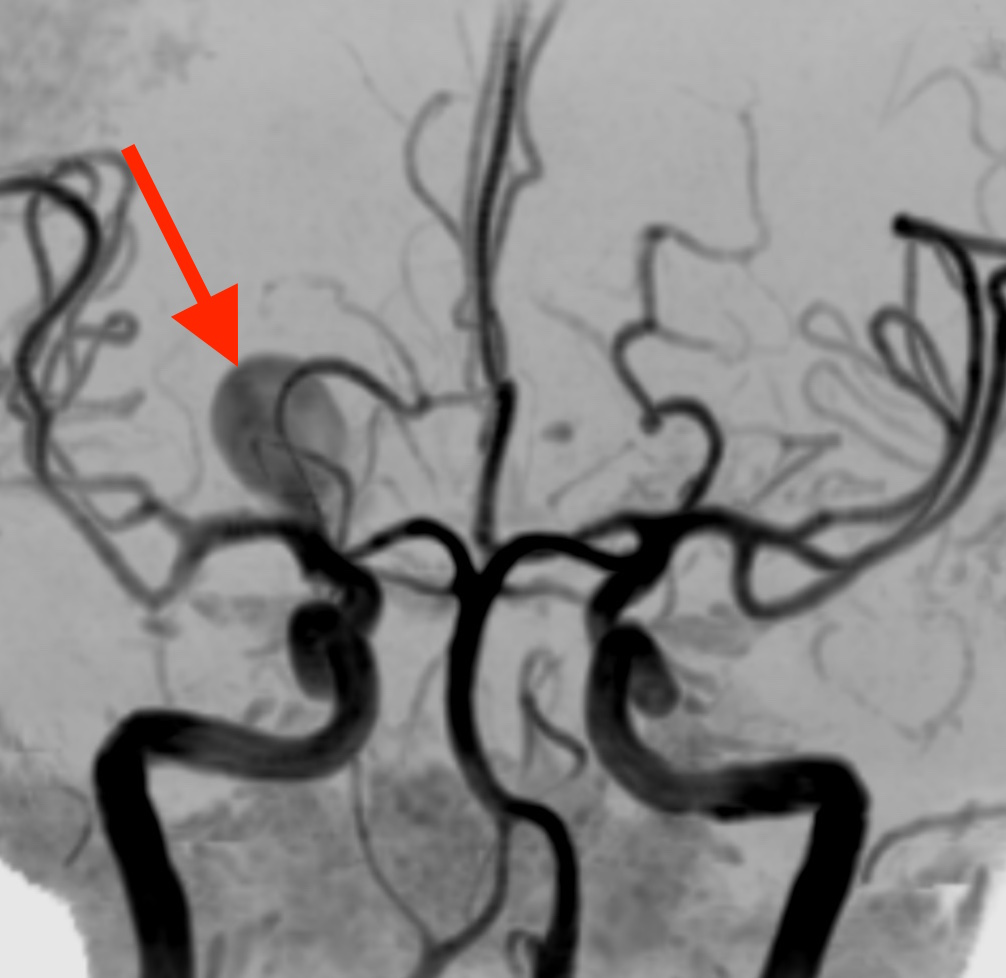

MRA(MRIを使った脳血管の撮像)を見たところ、右側の中大脳動脈という血管に直径約5cmの巨大脳動脈瘤が見つかりました。

脳動脈瘤は脳の動脈の一部がコブのように膨らんだもので、血管の壁が薄くなっているため破れやすくなっています。破裂した場合、くも膜下出血という非常に危険な状態となります。

発見された脳動脈瘤の場所は、たまたま右眼の裏側あたりですが、今回の右側の頭痛とは関係ありません。受診した時の症状はあくまで群発頭痛であり、まだ破裂していない状態なので頭痛の原因とはなりません。

直ちに手術の必要な状態であり、血圧を下げる薬を処方し、入院のできる脳神経外科を受診していただきました。